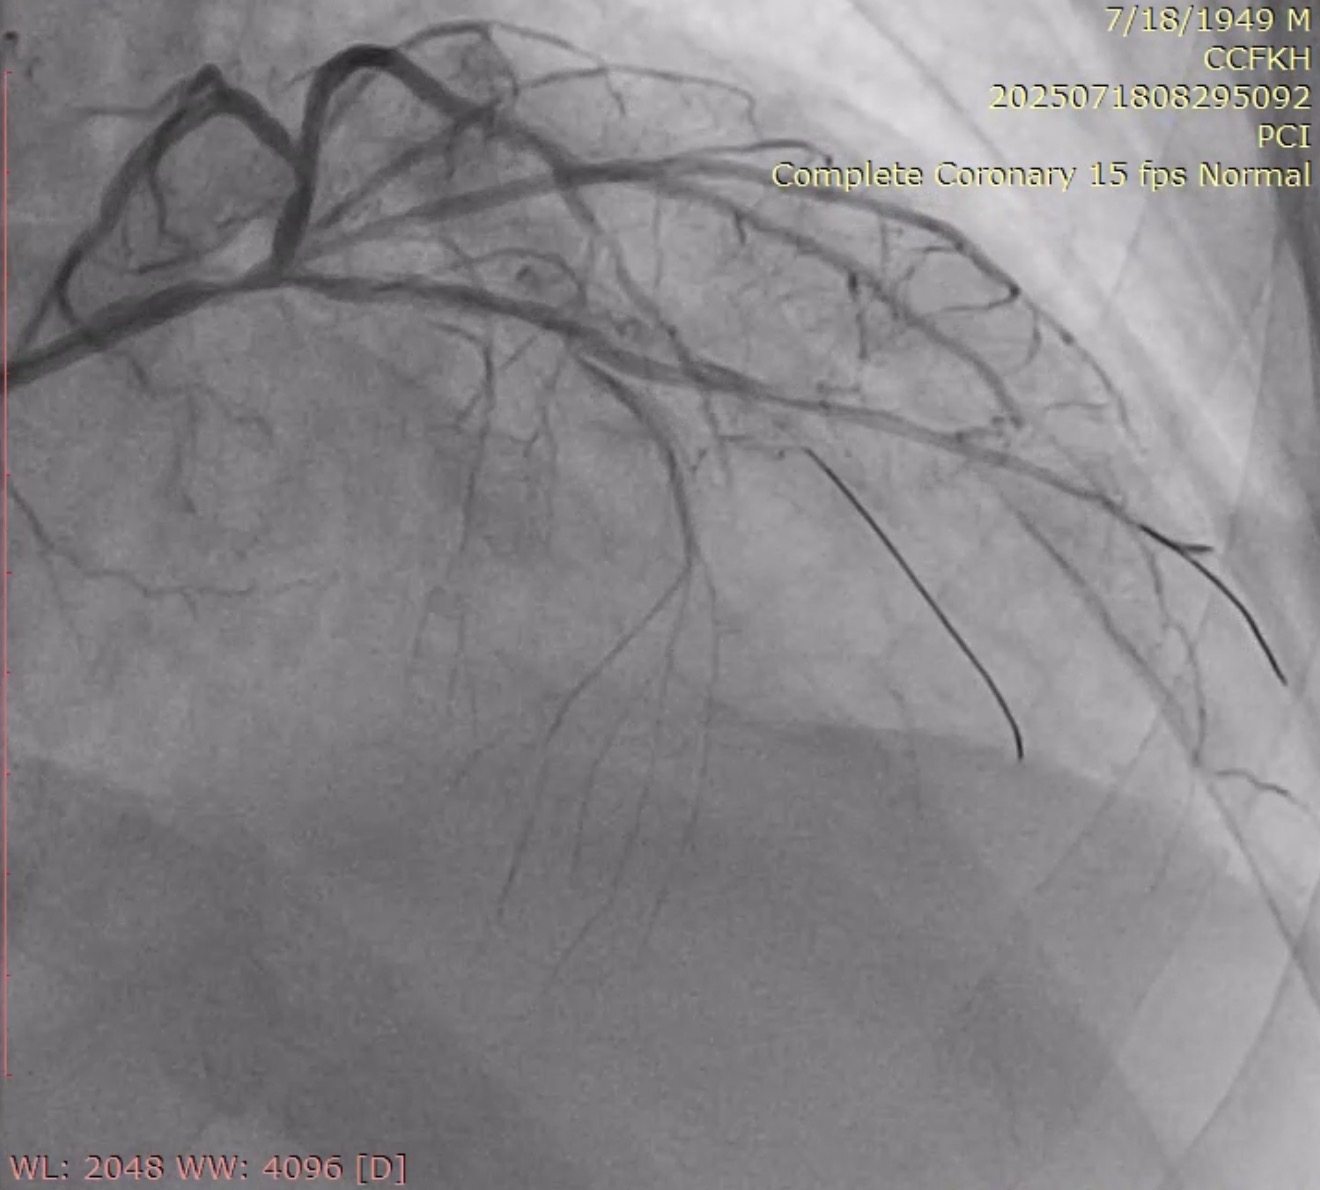

The left main was engaged by 6F EBU 3.5 via radial sheath. The LM occlusion was crossed by using workhorse guidewire (Cougar XT), suggesting an acute occlusion. Predilation with SC balloon (Sprinter Legend 1.5 x 12mm and Sprinter Legend 2.5 x 12mm) was performed at the occlusion site, resulting an antegrade flow from LM, but there was still no flow distally from mid-LAD.Plain old balloon angioplasty by Sprinter Legend 2.5 x 12mm performed at the mid-LAD, the flow from mid-LAD still was not achieved, giving the hypothesis of no reflow phenomenon. IC Nitroglycerine 100ug and IC Nicardipine 100ug were given several times, resulting a vasodilation and a better flow. It therefore revealed a significant competitive flow from powerful collaterals from the right coronary artery, ruling out the no reflow hypothesis (Refer to videos below for better illustration). Onyx Trucor DES 2.75 x 34mm, Onyx Trucor DES 3.0 x 22mm, and Onyx Trucor DES 3.5 x 22mm were implanted respectively from distal LAD to LM, and restored final TIMI 3 flow result

Case Summary